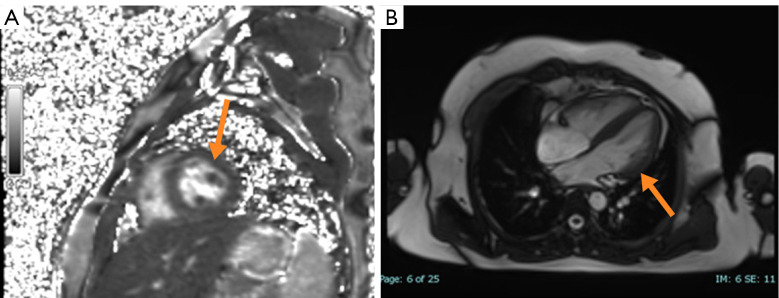

Case description: A 10-year-old boy with confirmed pulmonary paragonimiasis developed refractory pericardial effusion and markedly elevated IgG4 [11 g/L, 8.1× upper limit of normal (ULN)]. Despite five courses of praziquantel (75 mg/kg/day), effusions persisted for 8 weeks. Subsequent glucocorticoids (methylprednisolone 2 mg/kg/day) achieved rapid clinical resolution, though lacked histopathology IgG4-RD hallmarks. Longitudinal monitoring revealed a dynamic IgG4 decline (from 11 to 5.25 g/L) post-methylprednisolone therapy. However, residual IgG4 elevation (5.25 g/L, >3× ULN) and absent histopathological features of IgG4-RD left the diagnosis unresolved. Therapeutic monitoring revealed normalized eosinophils and imaging improvement, yet persistent IgG4 suggested potential immune dysregulation beyond parasitic clearance.